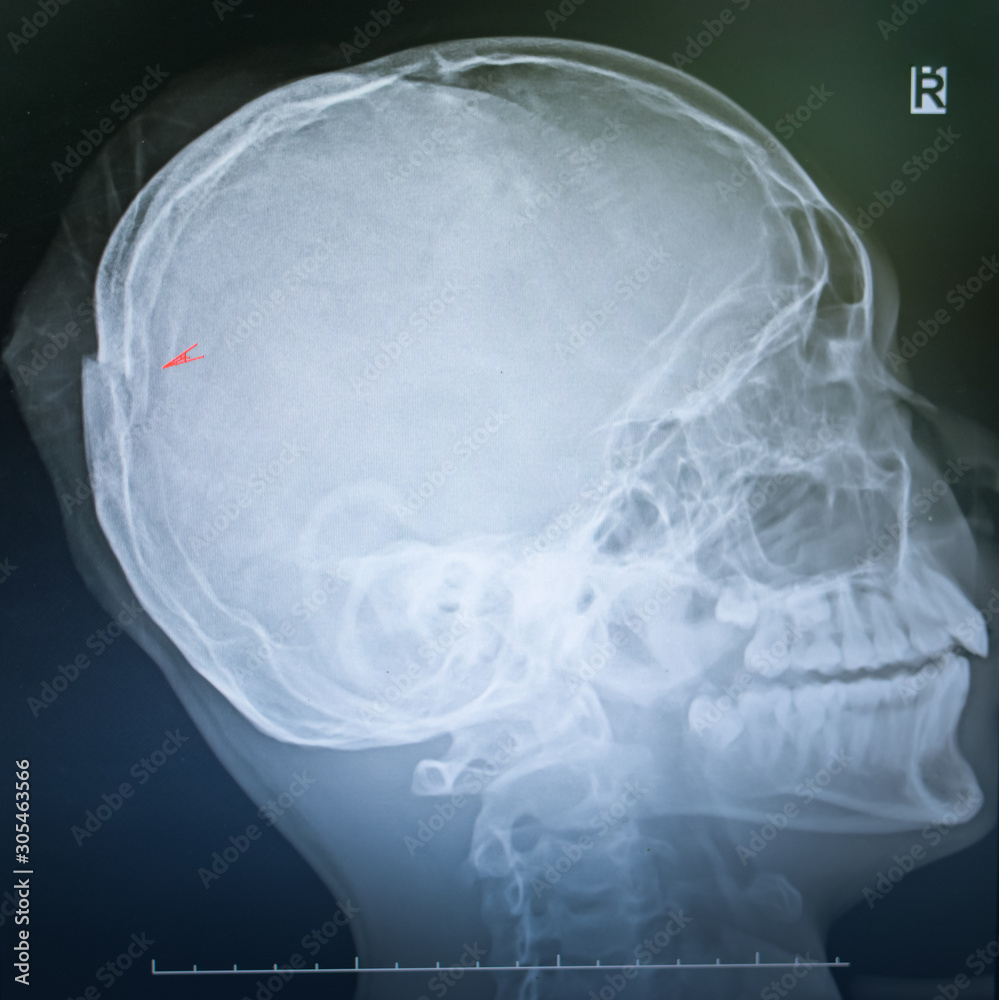

x ray film of a skull of a patient suffering from traumatic injury

x ray film of a skull of a patient suffering from traumatic injury Trauma X Ray Cases Traumas) or traumatic injury refers to damage or harm of sudden onset caused by external factors or forces requiring. The common terminology used for. Trauma series radiographs in a normal weight young adult with no injury detected. Note how the lung vessels can be traced. By sharing our collective experience through interesting and classic patient cases, we can make a. Trauma X Ray Cases.